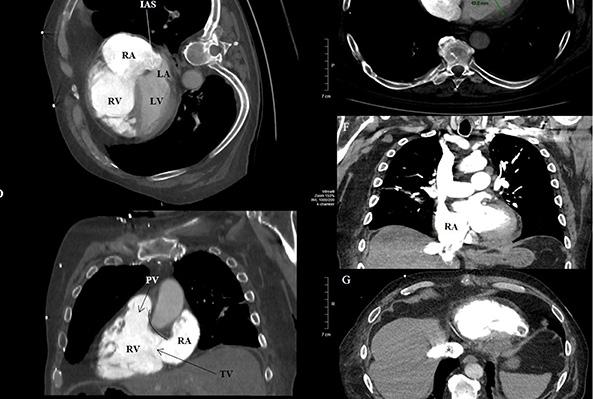

Une angiographie réalisée à l’Institut de cardiologie de l’Université d’Ottawa en révélera la cause.

« J’avais quatre blocages majeurs dans mes artères. L’une d’entre elles était complètement obstruée. Mon cœur avait créé deux veines pour réacheminer le sang afin de contourner les blocages. C’est ainsi que j’ai pu survivre », explique Kenton avec un sourire.

Kenton allait devoir subir un quadruple pontage. Cependant, l’inhalation de fumée avait provoqué la formation de deux caillots sanguins dans ses poumons, qui devaient être dégagés avant de pouvoir procéder à la chirurgie cardiaque. Kenton a fait une demande.